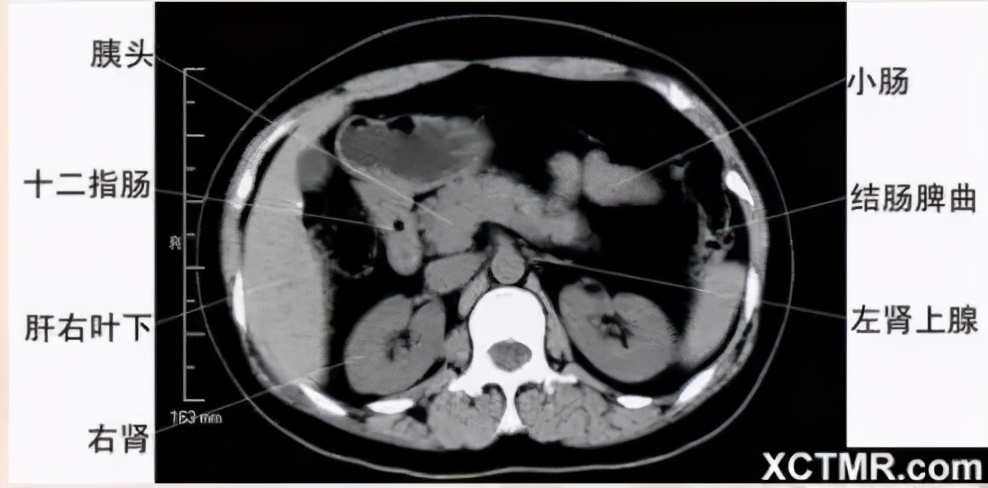

腹部CT